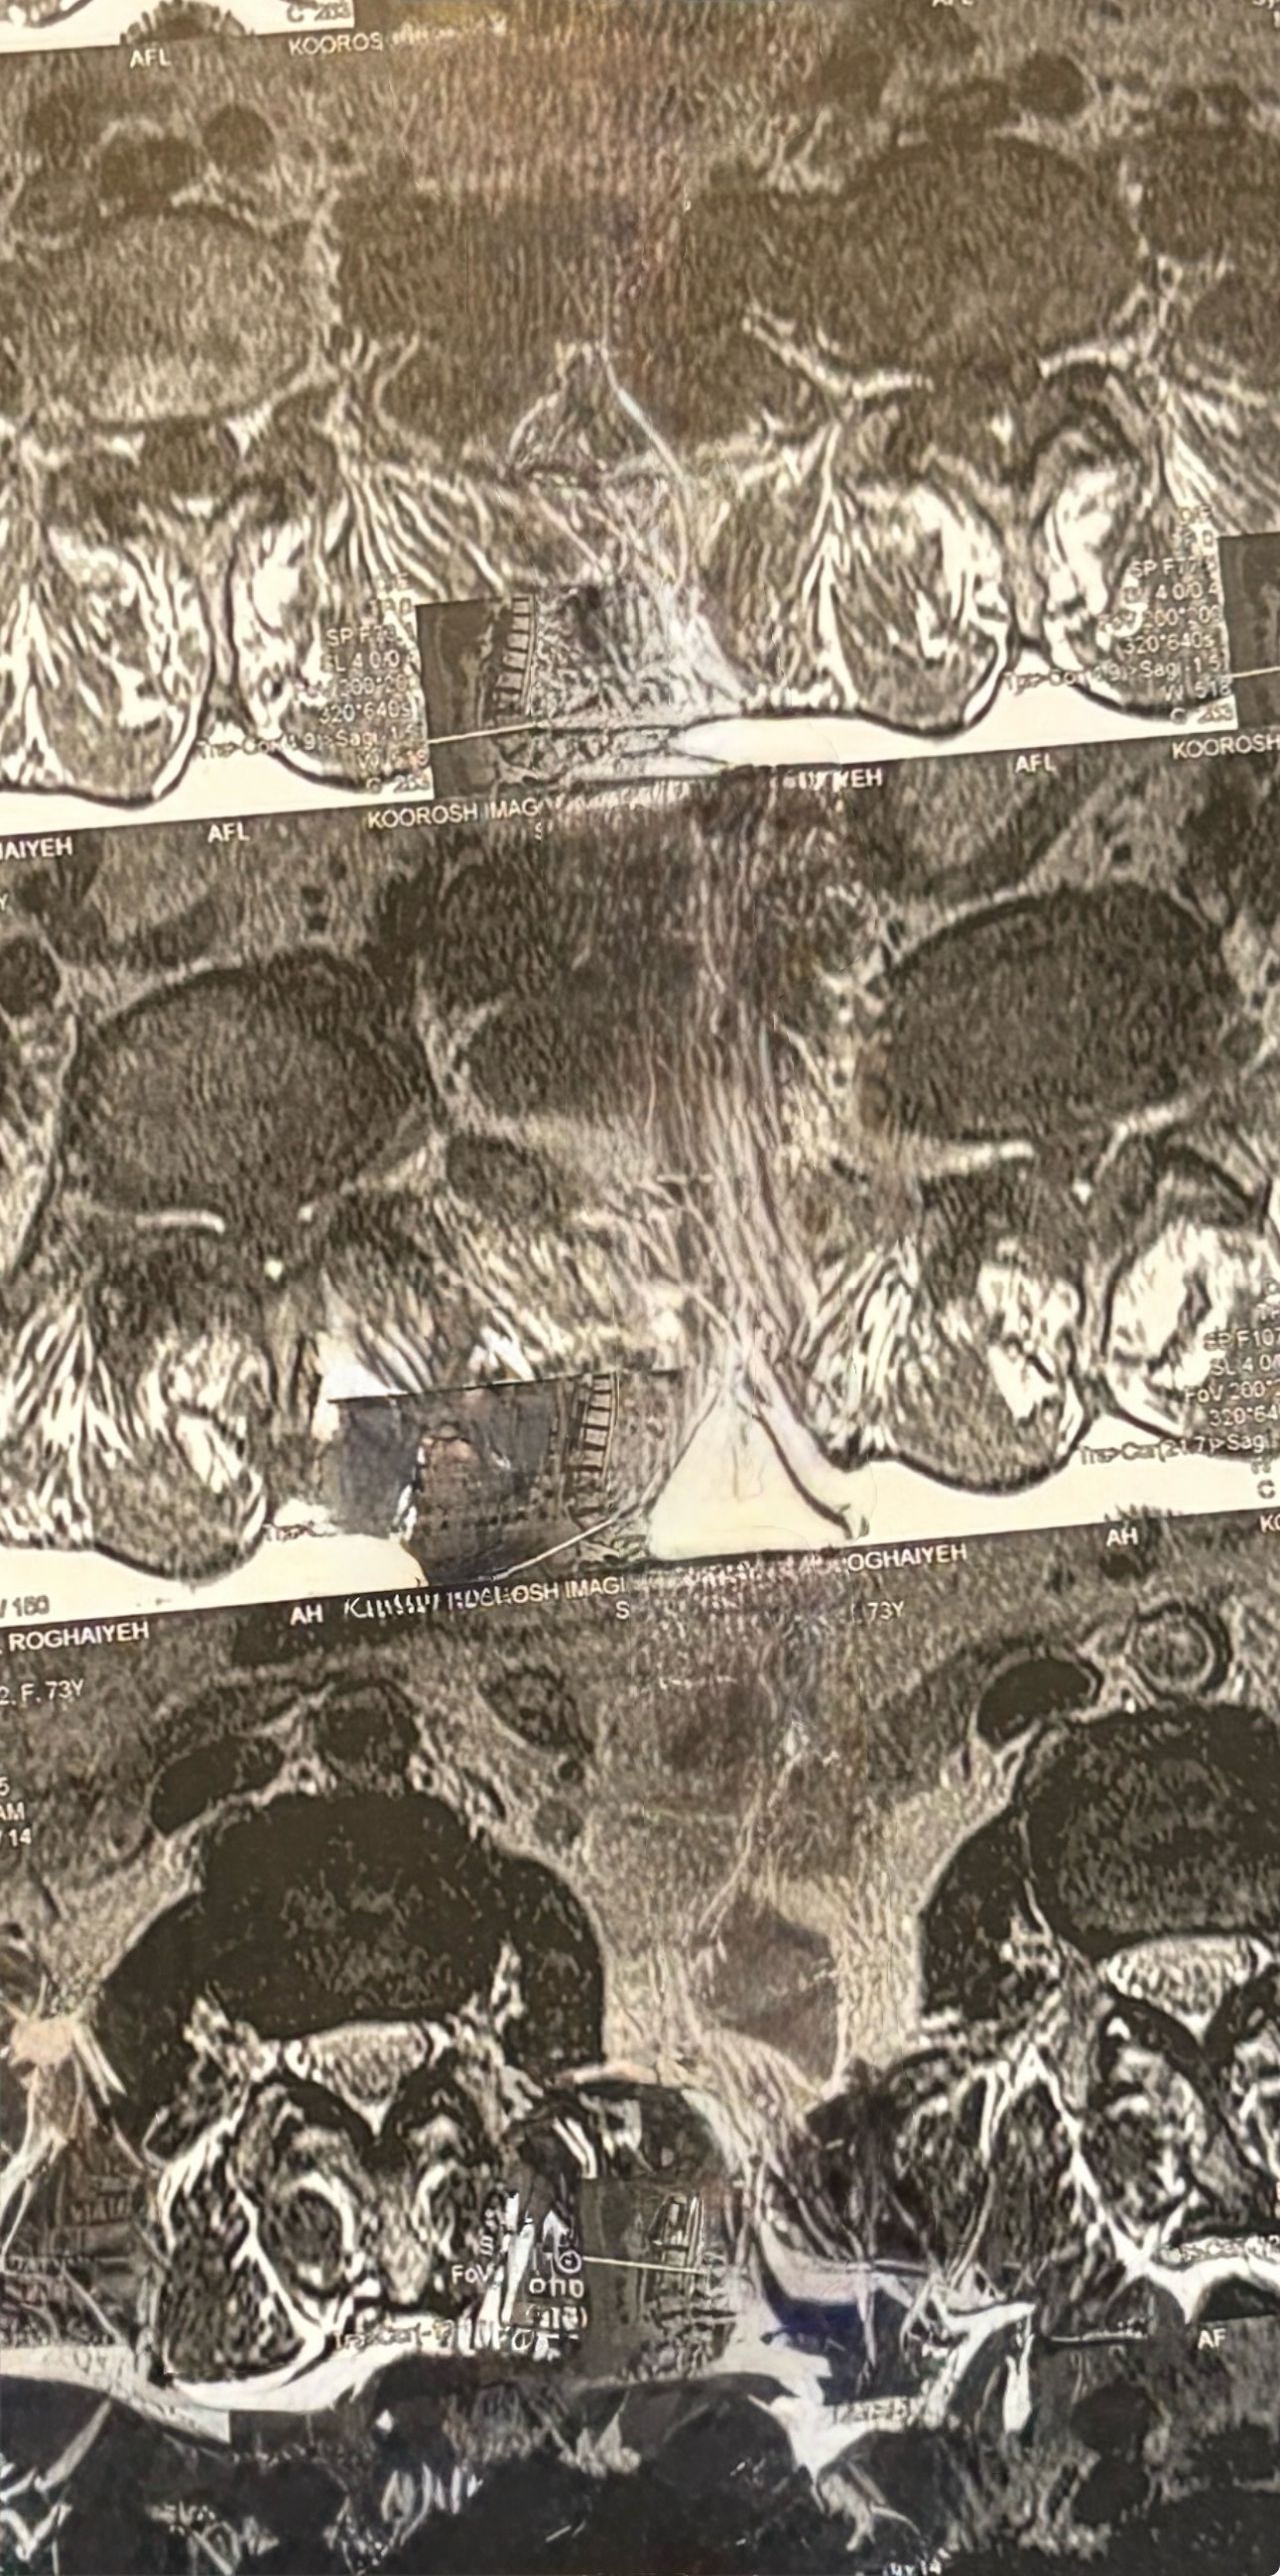

41 years old man presented to my clinic in October 2023 with acute and sever R neck pain with radicular pain to his R upper extremity along C6 dematom since 2 weeks ago. Examination didn’t show any upper motor signs. Was suggested urgent surgery

I ordered EMG/ NCV : showed mild R C6, C7 irritation without any active axonal loss

In his MRI was reported R. para R. IVF Massive extrusion. I decided to control his pain and manage this patient with reevaluation of patient every other session. For 5 sessions i just used acupuncture and laser and IFC and mild adjustments to his R. T3-T7 and mild arthosteem to above and below involved segment. Cervical adjustment considered contraindicated for this patient. From session 6th- 8th i started to use mild/gentle cervical decompression. He used soft cervical collar all the time. His pain decreased by 80 percent

I gave him cervical traction pump to be used 3-5 times per day at home for the next 3 months and i released the patient. He was evaluated every week once for one month and after that every 2 weeks. After 3 month I repeated MRI. Size of the herniated disc was reduced greater than 50 percent. Asked him to do another mri in 6 months

In general: Precise selection of the patients, examination,diagnosis, plan of management, reevaluation and treatment can be done by doctors of chiropractic for the patients with spinal disc herniation and stenosis Moreover giving reasonable time to these kind of patients under direct supervision by their chiropractic doctors can prevent unnecessary surgery. Proper selection of these kind of patients is another important fact that can be done precisely by chiropractors.

MRIs before and after proper management of this patient: